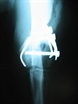

snímek 5: RTG - DV projekce

snímek 6: RTG - LL projekce